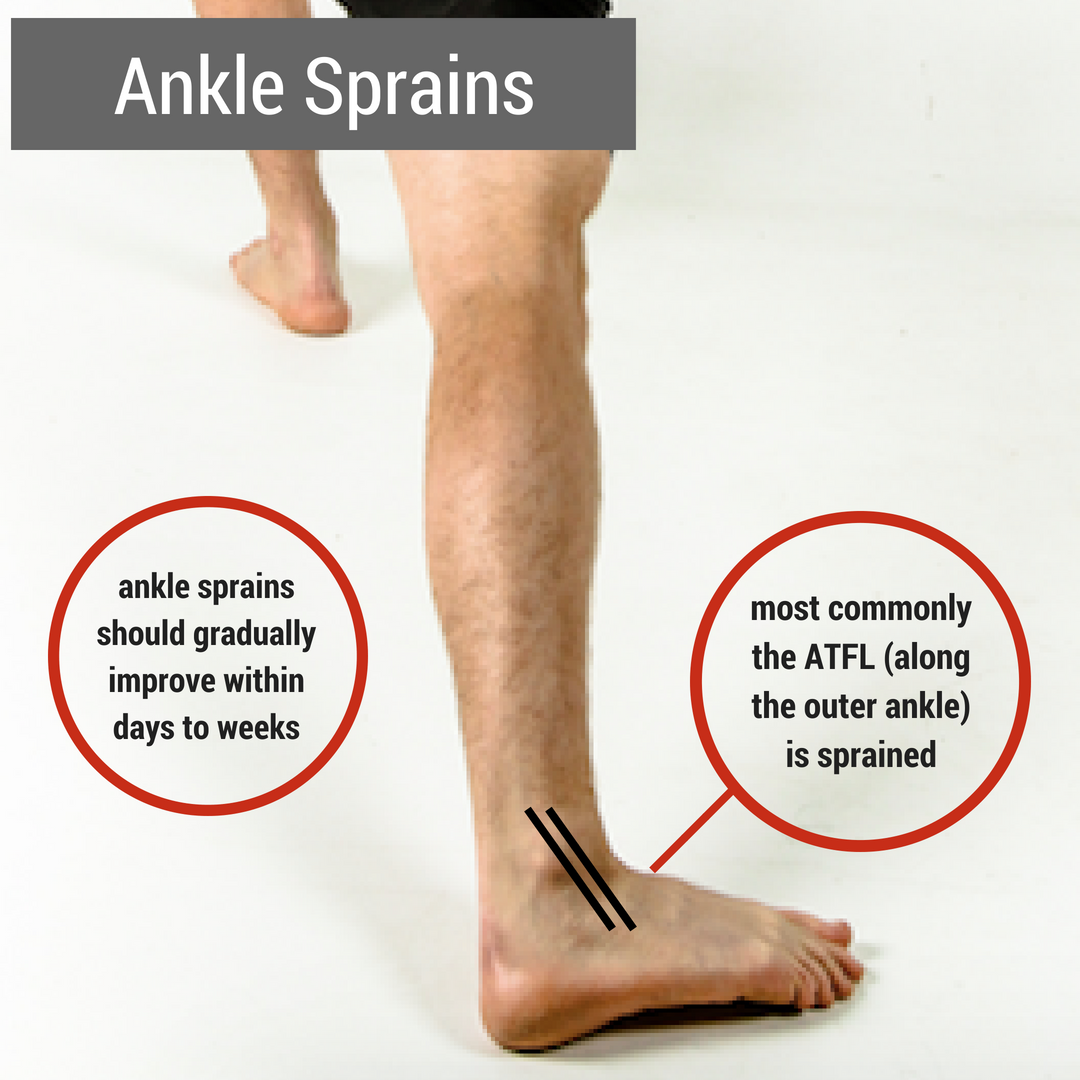

Due to its low ultimate load and the anatomical positions of origins and insertions, the ATFL is most commonly injured in a lateral ankle sprain [30]. The subtalar joint is formed by the articulation between the bottom of the talus and the calcaneus [18].

The three ligaments that compose the lateral complex are the anterior talofibular (ATFL), the calcaneofibular (CFL), and posterior talofibular (PTFL) and they tend to be injured in this order with the anterior talofibular ligament being injured most commonly.

What movement does the anterior talofibular ligament prevent?

It is one of the lateral ligaments of the ankle and prevents the foot from sliding forward in relation to the shin. It is the most commonly injured ligament in a sprained ankle—from an inversion injury—and will allow a positive anterior drawer test of the ankle if completely torn.

Because of its lateral position in the ankle, the anterior talofibular ligament absorbs most of the negative impact when the foot is planted unnaturally or when the ankle twists in an awkward way. The sprains to this joint that occur from it being stretched beyond its means are typically mild. However, if the ligament becomes slightly ...

Which ligament is the weakest in the ankle?

What is the most common injury in college athletics?

Ankle ligament sprains were also reported to be the most common injury for college athletics in the United States. The anterior talofibular ligament is the most commonly injured ligament in the ankle.

What is the weakest ligament in the lateral collateral complex of the ankle?

Approximately two-thirds of ankle sprains tend to be isolated injuries to the anterior talofibular ligament (ATFL), the weakest ligament in the lateral collateral complex of the ankle. There is general agreement that avulsion is more common at the fibular than the talar end of the ligament 2.

What is the most common ligament injury?

Anterior talofibular ligament injury is the most common of the ligament injuries that can occur as part of the lateral ligament complex injuries 2. The injuries can comprise either soft tissue tears, avulsion fractures or both.